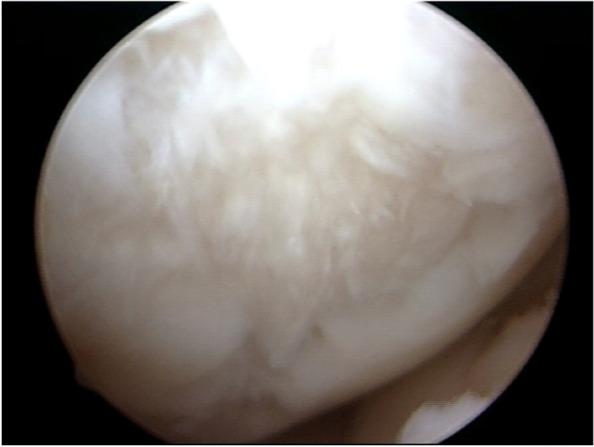

Fig. 1.

Patellar cartilage lesion in the entire lateral facet, grade 4 ICRS. 113 × 85 mm.2 (150 × 150 DPI)